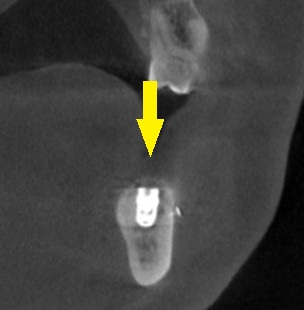

本日、2本のインプラント埋入と、骨造成術を行いました。

下の写真3段目が手術後のCTです。

インプラントと神経までの距離は確保され、インプラント上方は人工骨で覆われています。